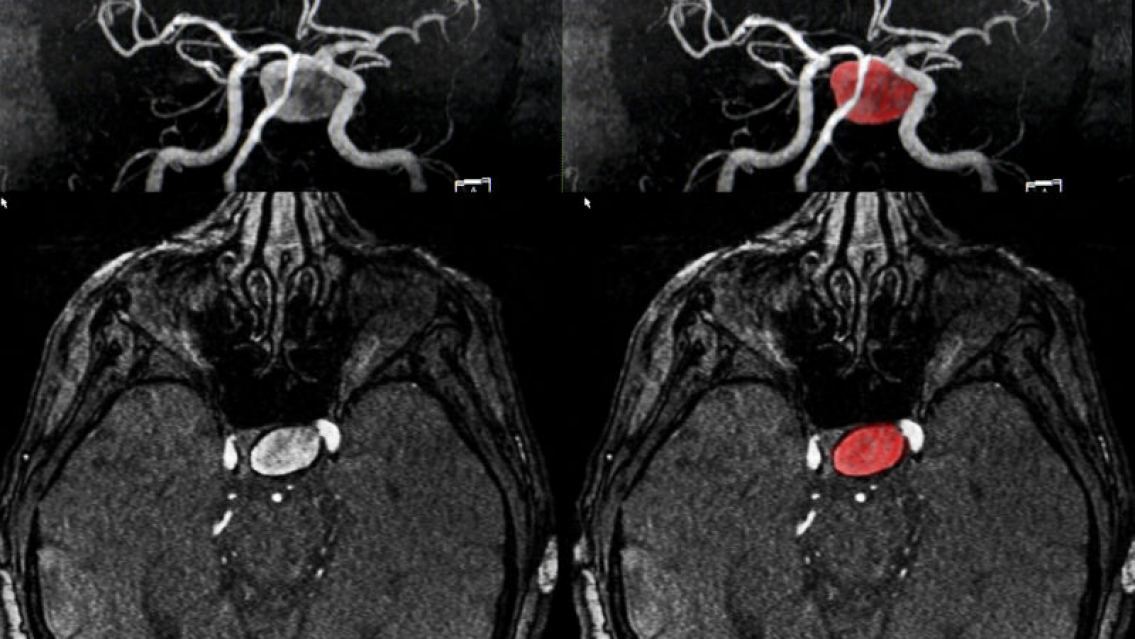

A los 18 años, Ella Pick experimentó lo que creyó ser un malestar producto de la resaca durante unas vacaciones con amigas. Sin embargo, al regresar a casa y retomar su rutina, sus síntomas se intensificaron. Migrañas persistentes y el hundimiento de su ojo izquierdo la llevaron a buscar ayuda médica, donde recibió la devastadora noticia de que tenía un tumor cerebral incurable e inoperable. Le dieron un pronóstico de vida de solo 12 meses.